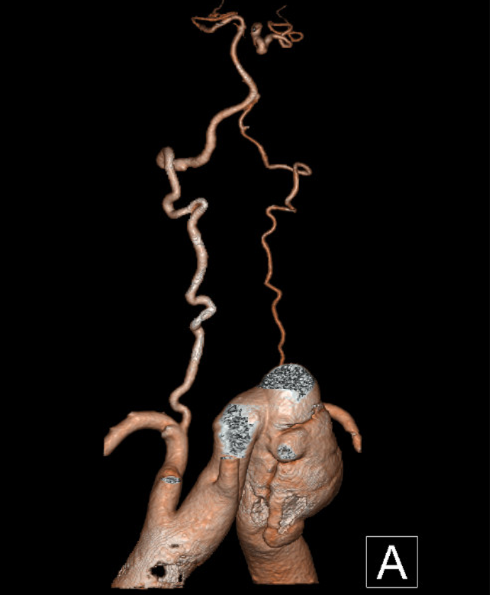

CTA检查

1、Ⅲ型弓,主动脉弓部远心端可见夹层动脉瘤,瘤体44mm*79mm,左锁骨下动脉发自瘤体下方降主段,且萎缩狭窄。

2、右椎动脉绝对优势,左椎动脉萎缩狭窄。